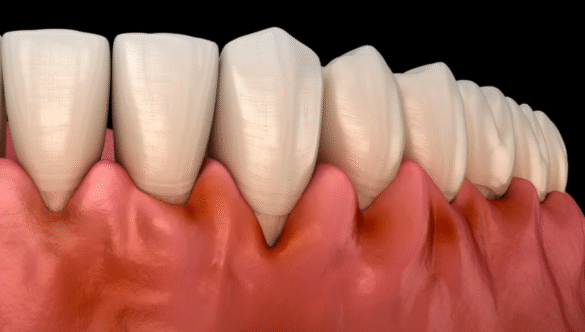

Treatments At Our Dental Clinic in Gandhinagar

Whether you’re searching for a “toothache treatment near me”, “best dental implants near me”, or simply need a trusted dental clinic near you in Gandhinagar, Nova Dental Hospital has the right solution.